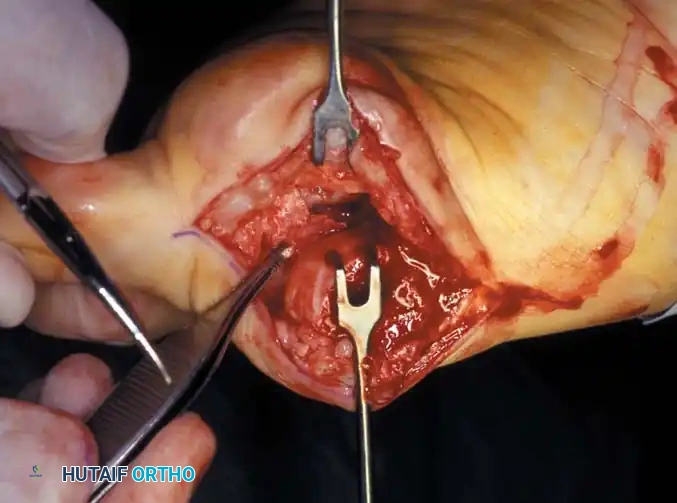

• Using a Freer elevator or a small osteotome for its strength, mobilize the fi bular sesamoid (Fig. 78-31A to C). This may be diffi cult in elderly patients with signifi cant deformity and adherence of the sesamoid to the metatarsal head. Lift the metatarsal dorsally for exposure (Fig. 78-31D and E).

Fig. 78-31 Excision of fi bular sesamoid in modifi ed Keller procedure. With base of proximal phalanx removed and medial eminence excision, exposure of fi bular sesamoid is not as diffi cult from medial incision. A, Operative photograph showing elevation of fi rst metatarsal with strong two-tooth retractor and use of small osteotome to mobilize fi bular sesamoid and lateral capsuloligamentous (frequently contracted) structures. Osteotome is between metatarsal head and lateral sesamoid. When mobilization of fi bular sesamoid is complete, entire sesamoid is visible for excision. Note chondromalacia of tibial sesamoid articular surface medial to osteotome. B, Fibular sesamoid has been excised, and lateral capsular structures and conjoined tendon (in forceps) have been released. Neurovascular bundle to lateral side of hallux is adjacent to these structures. C, Diagrammatic representation of modifi ed Keller procedure. By excising fi bular sesamoid, valgus moment of conjoined tendon of fl exor hallucis brevis and adductor hallucis no longer pulls fl exor hallucis longus tendon laterally (carrying hallux with it) through capsulosesamoid plantar plate and pulley system. D, Metatarsal head must be lifted dorsally to excise fi bular sesamoid under direct vision. E, Note exposure of fi bular sesamoid after mobilization of metatarsal head. Continued